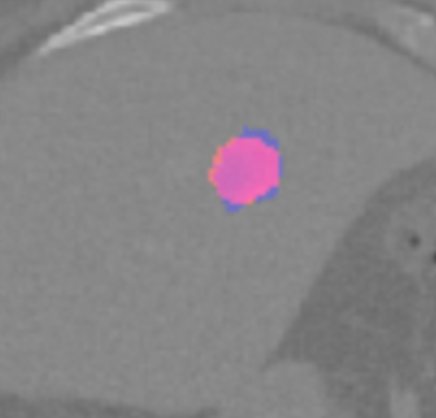

Each pixel of the image is assigned to one of the two classes liver/other tissue and tumor/other tissue, respectively, with a certain probability. Results of the automated liver and tumor segmentation are visualized in Figure 3.2. Comparison with ground truth and segmented liver and tumor give rise to the assumption that our approach is highly promising for obtaining high performance metrics. To qualitatively evaluate performance, we applied some of the commonly used evaluation metrics in semantic image segmentation. Performance metrics are summarized in Table 1.